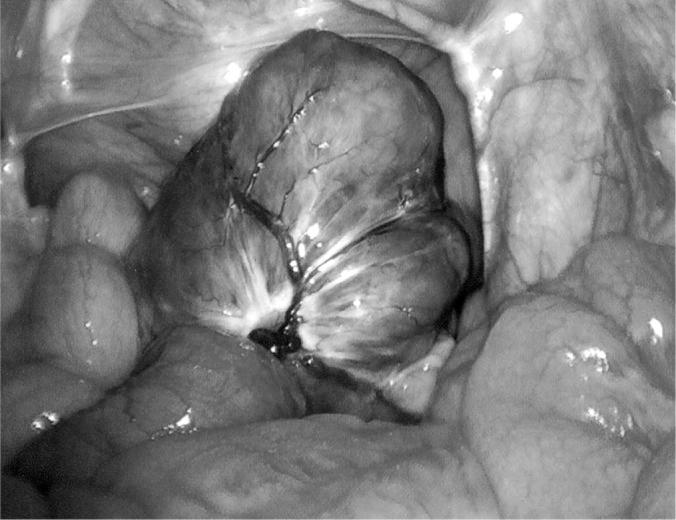

Two patients presented to the emergency department with signs and symptoms of small bowel obstruction. On workup, each was found to have a solid lesion either within or adjacent to the small bowel at the point of obstruction and both were emergently taken to the operating room. The pathologic diagnosis of small bowel GIST tumor was the same in both cases, but the pathophysiologies of the obstructing tumors were different.

Both patients underwent laparoscopic surgery with successful resection of the lesions. The details and crucial points of the laparoscopic approach to these tumors are described with specific attention to its appropriateness and safety in treating GIST tumors. Attention to particular details of the manipulation and management of the bowel in the face of obstruction and removal of the lesions is described.